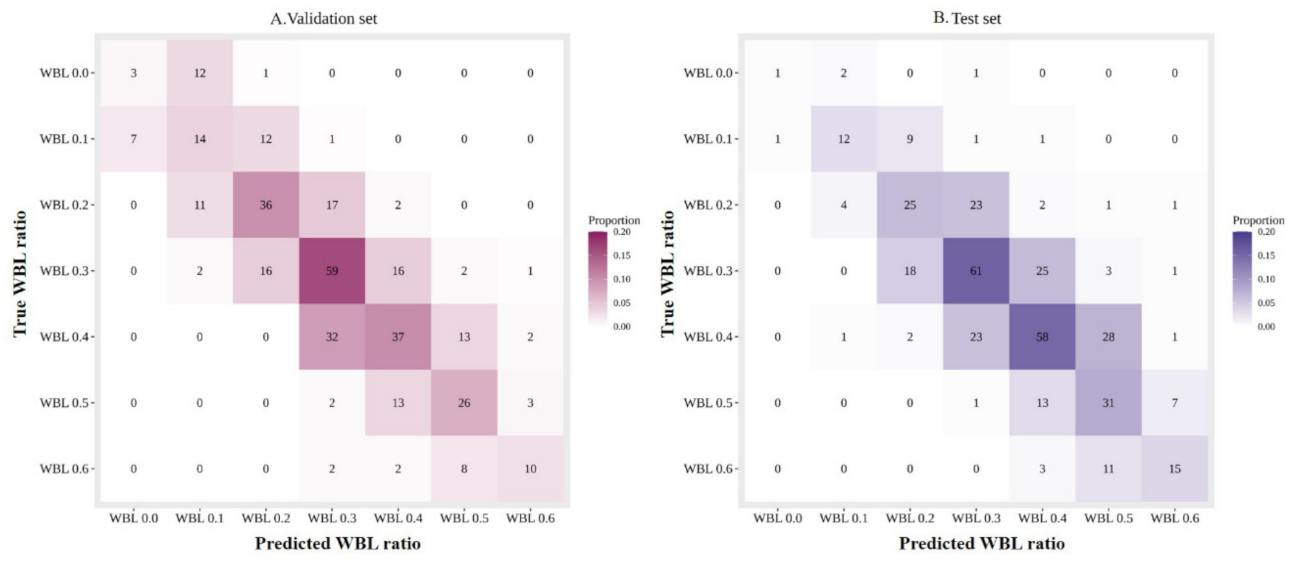

3. Results

| MAE | 0.054 | 0.054 |

| CS (0.1) | 0.953 (345/362, 0.924–0.970) | 0.951 (367/386, 0.924–0.970) |

| CS (0.0) | 0.511 (185/362, 0.458–0.564) | 0.526 (203/386, 0.474–0.577) |